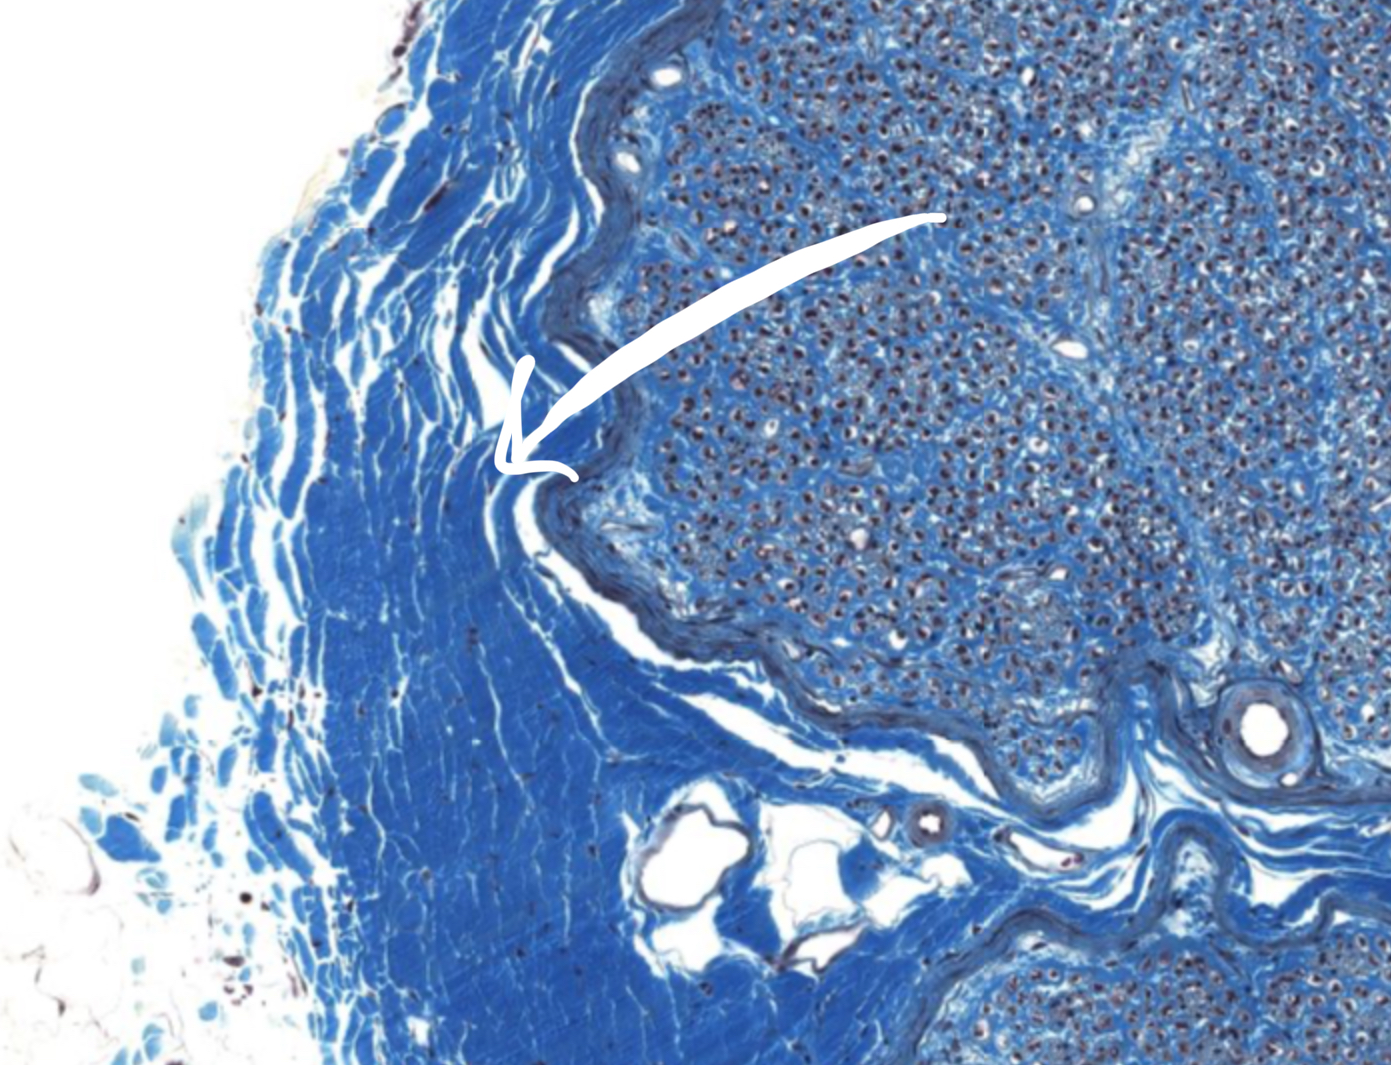

What is this structure

Epineurium of peripheral nerve

Perineurium of peripheral nerve

Endoneurium of peripheral nerve